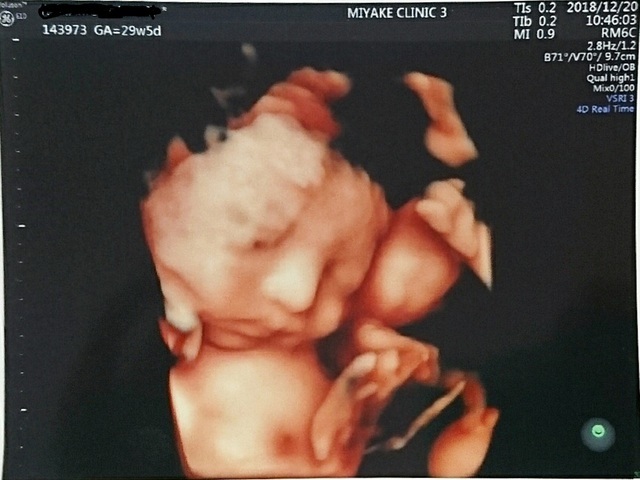

29週0日(29w0d・女の子)|みちゃこ88 さん(28歳)

エコー写真撮影時のエピソード:

初めて顔がはっきり見えました!小さいと言われてて心配だったけど、ぷっくりしてきて安心しました。

でも膀胱炎になってしまってたくさん水分を取るようになったのでトイレが近くて夜何回も起きてしまいます( ; _ ; )がんばって乗り越えよう!